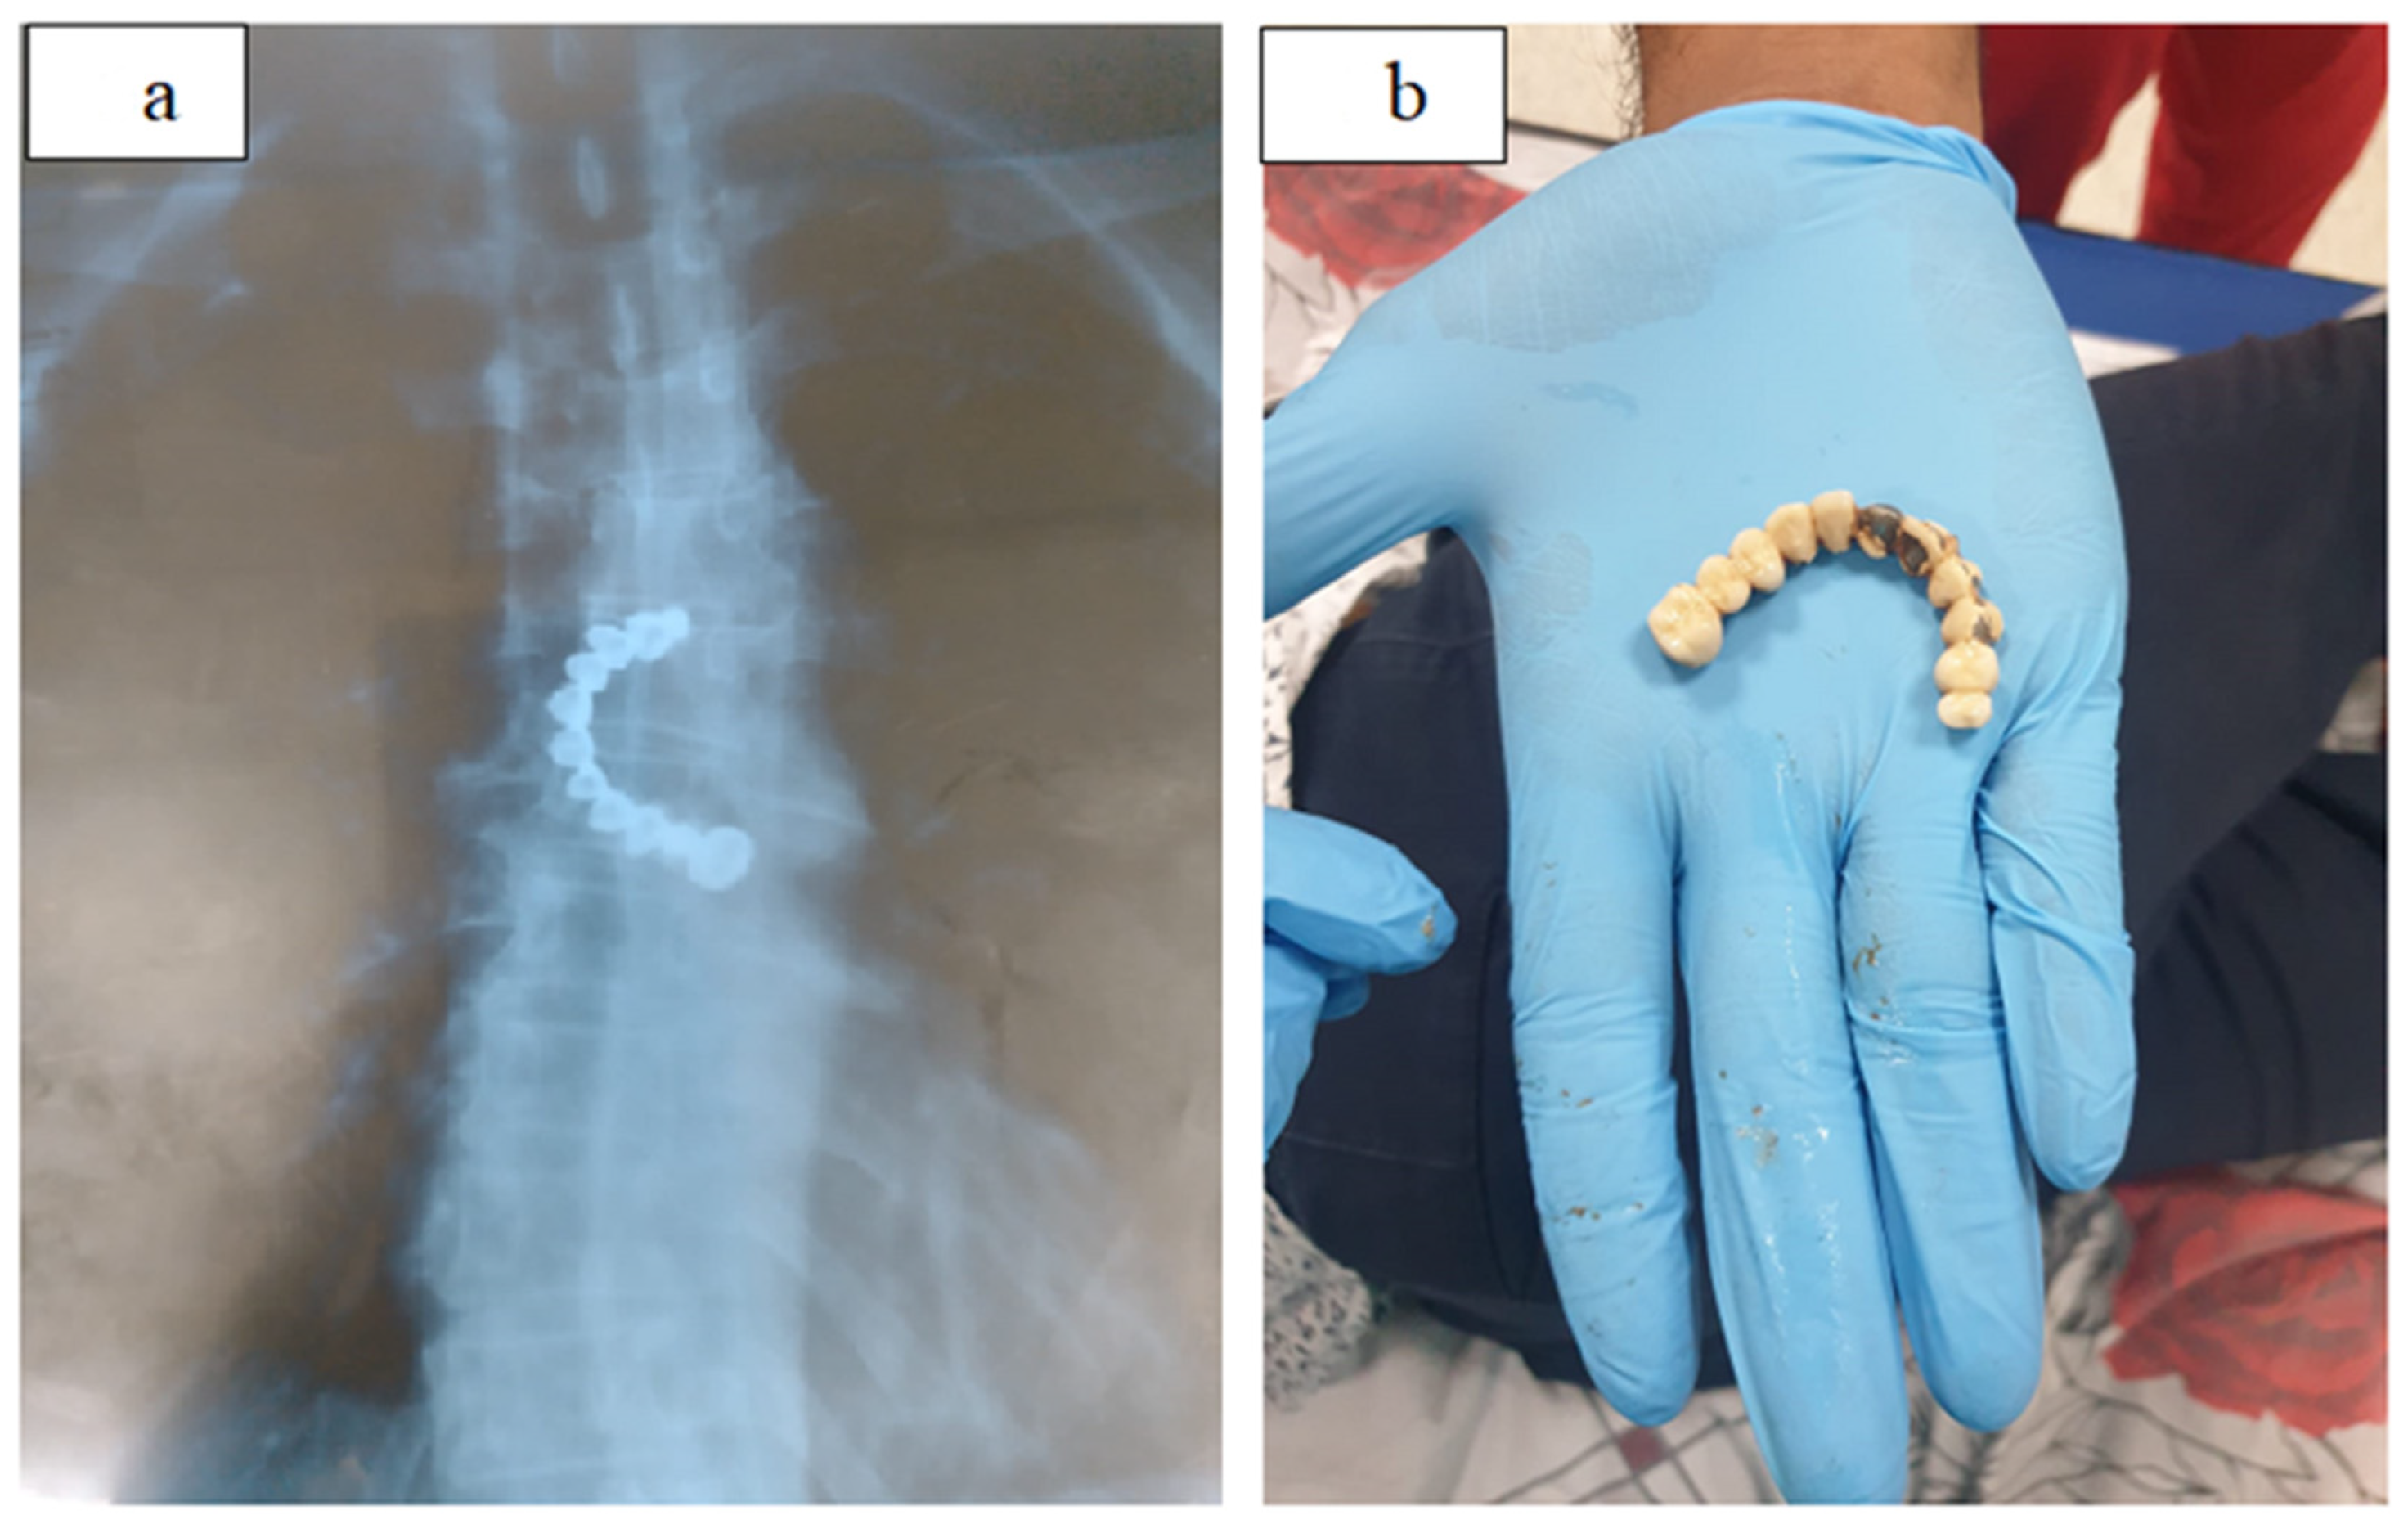

| Cutting objects | Thin objects: needles, toothpicks, pins, razor blades, crushed glass, partial dental plaque |